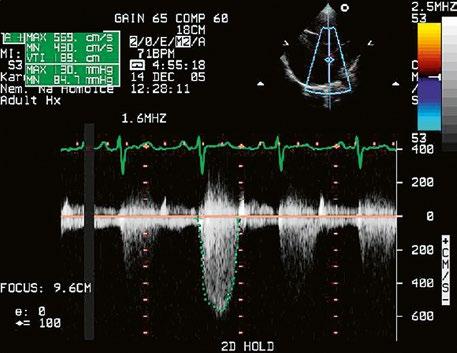

Obr. 45.44 Pacientka s těžkou, dlouhodobě neřešenou valvární a subvalvární stenózou plicnice (také Obr. 45.45 ) s extrémně těžkou hypertrofií přední stěny pravé komory (označena zelenými křížky a šipkou, šíře stěny PK18 mm). Hypertrofie myokardu infundibula přispívá k sekundární subvalvární stenóze plicnice. M mode, parasternální dlouhá osa.

AO – aorta, LK – levá komora, LS – levá síň, PK – pravá komora

Obr. 45.45 Těžká, dlouhodobě neřešená valvární a subvalvární stenóza plicnice s vysokým gradientem 155/82 mmHg (CW doppler) (viz též Obr. 45.44)